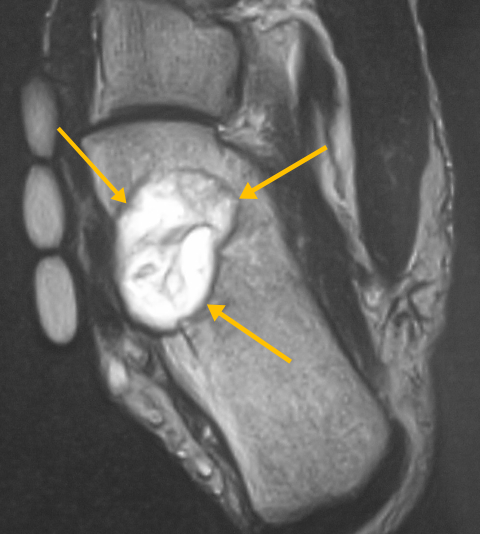

Radiographic imaging is used to help form a diagnosis of CMF. These include, X-Ray, MRI, CT and Bone Scans. An example of a CMF MRI is shown.